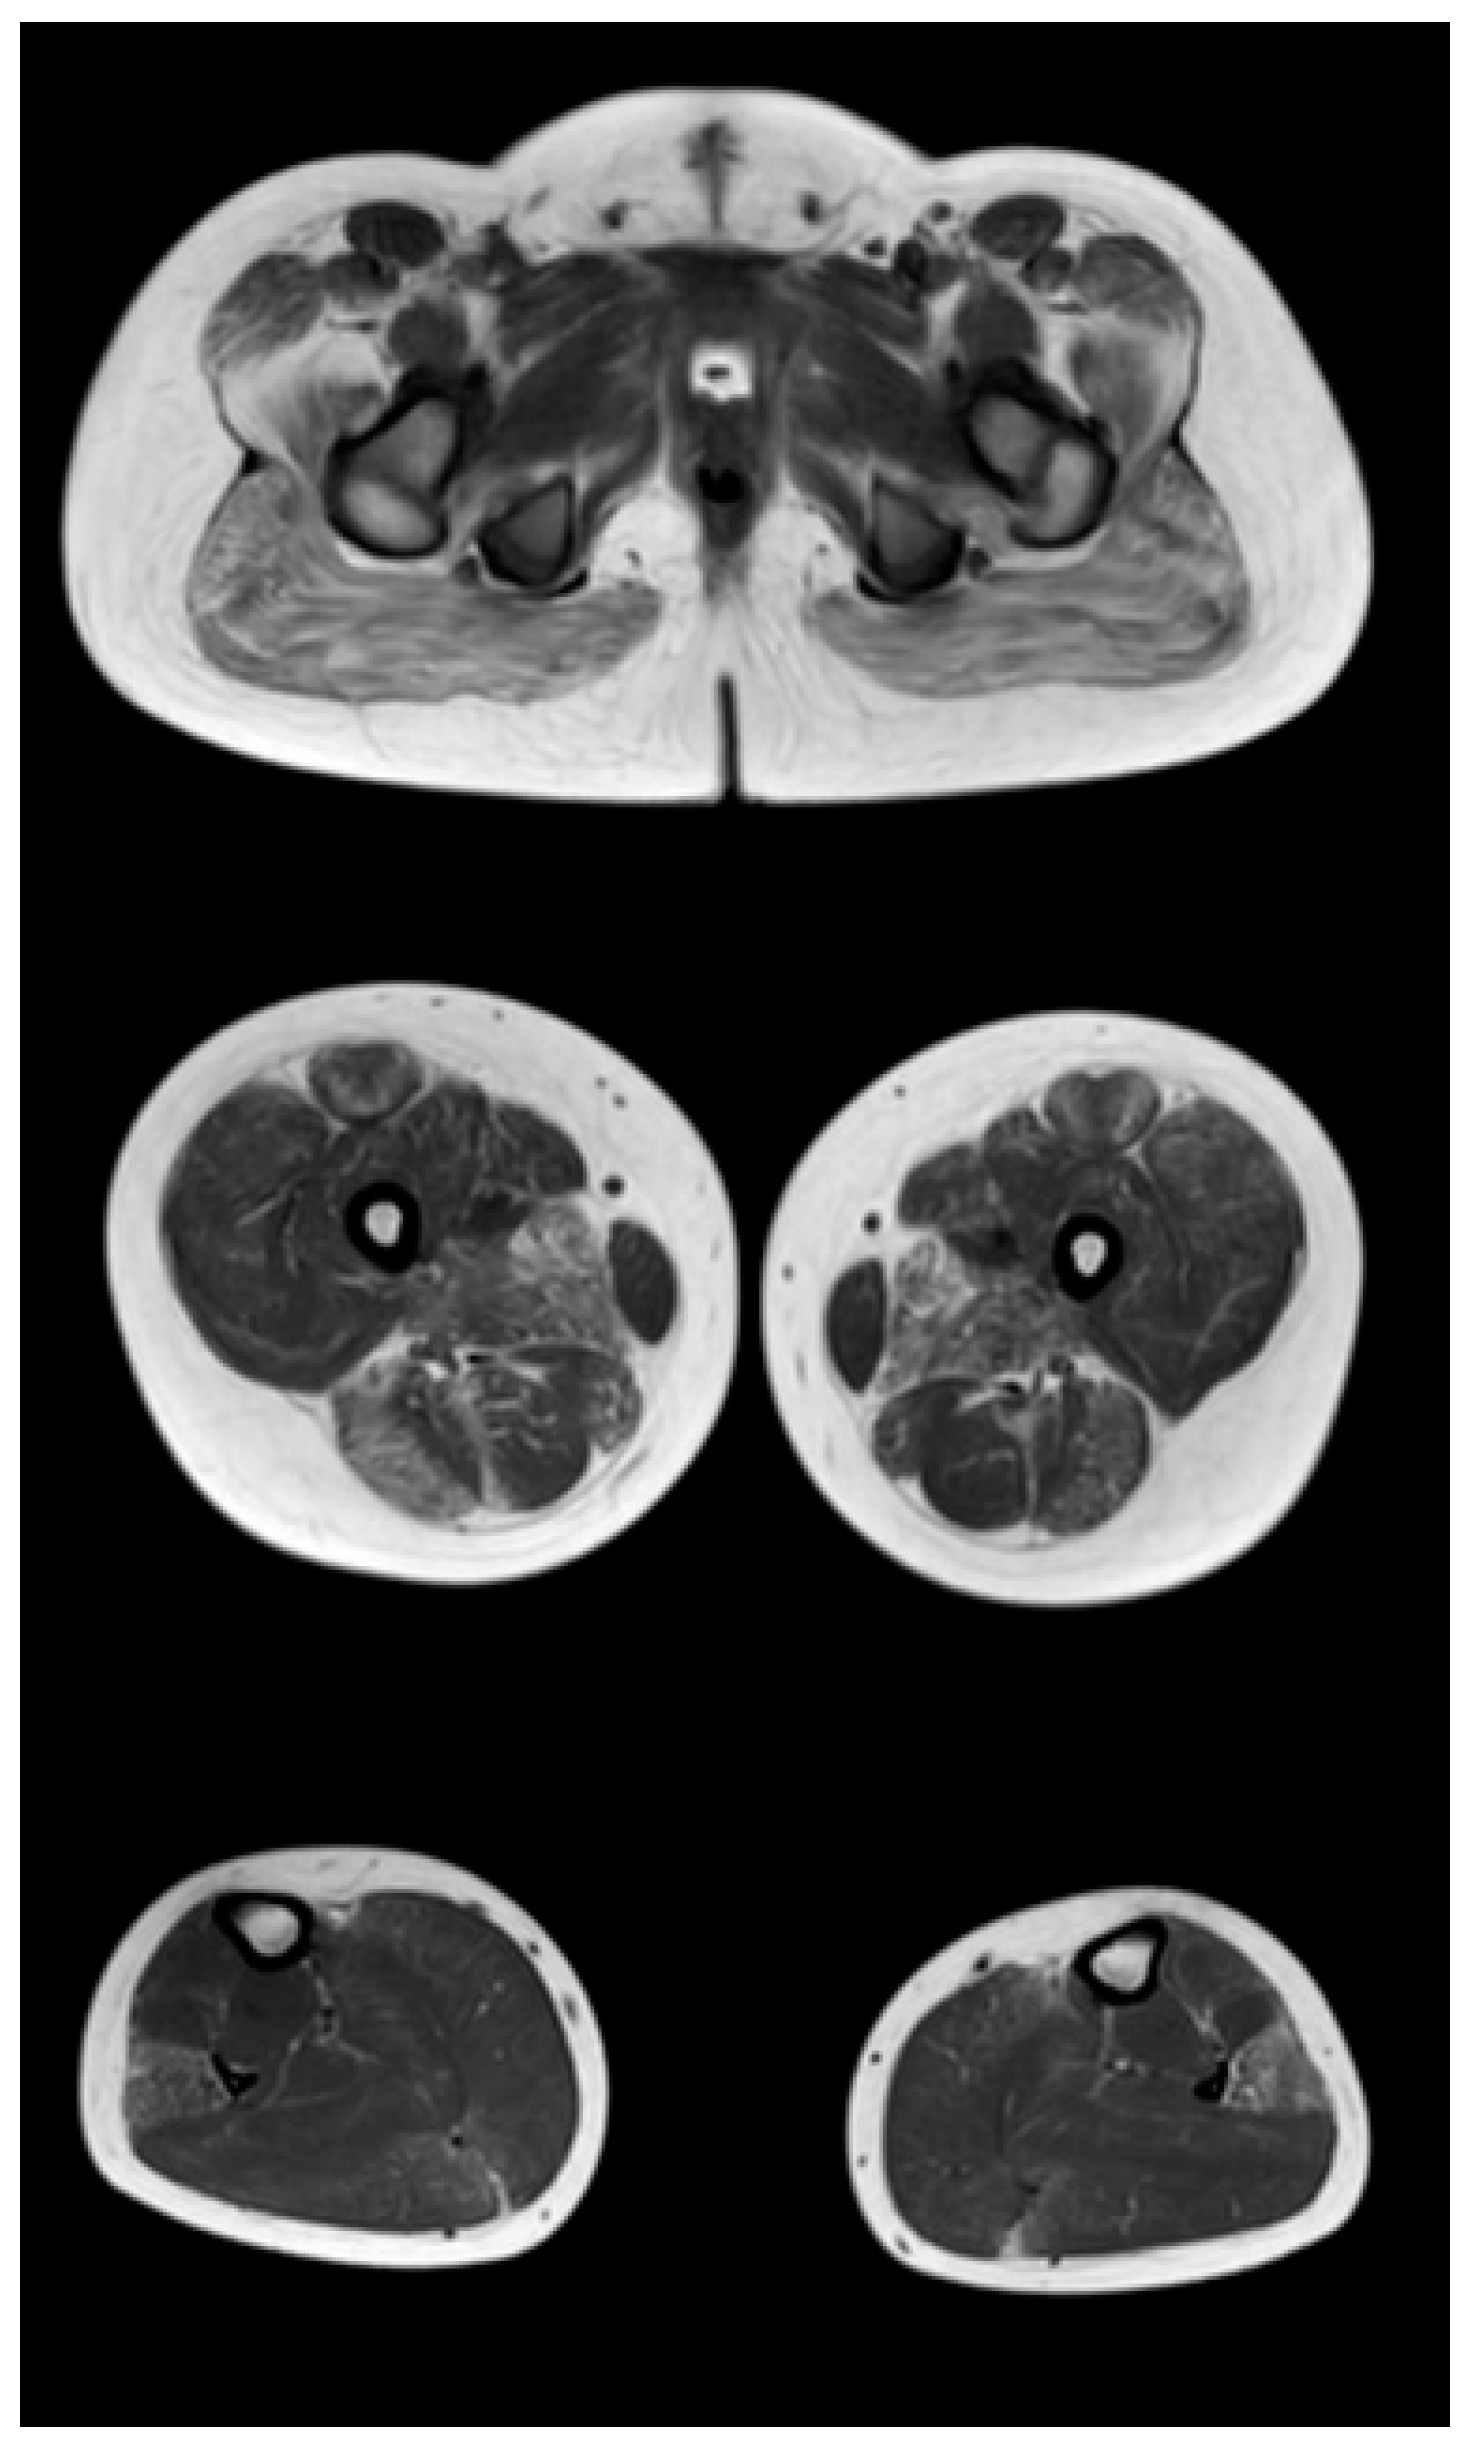

Comparative results of assessing the severity of fibro-fatty degeneration of muscles according to the Mercuri scale (point) of patients in accordance with clinical examples (Figure 3, Figure 4 and Figure 5) are presented in Table 6. For comparison of MR patterns in DMD, Figure 6 shows images of the pelvic level, femoral level, and lower leg level of healthy subjects (volunteers). In contrast to the pathological condition, a clear symmetry, uniformity of the density of muscle tissue, organs of the pelvic level, and the absence of pathological formations draw attention.

Figure 6.

MR images of healthy volunteers 13 years old (left) and 8.3 years old (right). From top to bottom: the pelvic level, the femoral level and the level of the legs.